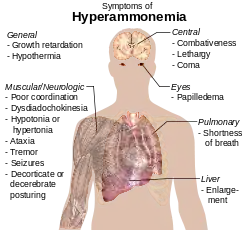

En fisiología

El amoníaco también juega un papel en las fisiologías normal y anormal. Es biosintetizado a través del metabolismo normal de los aminoácidos y es tóxico en altas concentraciones.[62] El hígado convierte amoníaco a urea a través de varias series de reacciones conocidas como el ciclo de la urea. Disfunciones en el hígado, como la cirrosis, pueden llevar tener una cantidad alta de amoníaco en la sangre (hiperamonemia). Del mismo modo, defectos en la enzima responsable del ciclo de la urea, como la ornitina transcarbamilasa, pueden provocar hiperamonemia. La hiperamonemia lleva a la confusión y a un estado de coma de encefalopatía hepática, así como las enfermedades comunes en personas con problemas en el ciclo de la urea.[63]